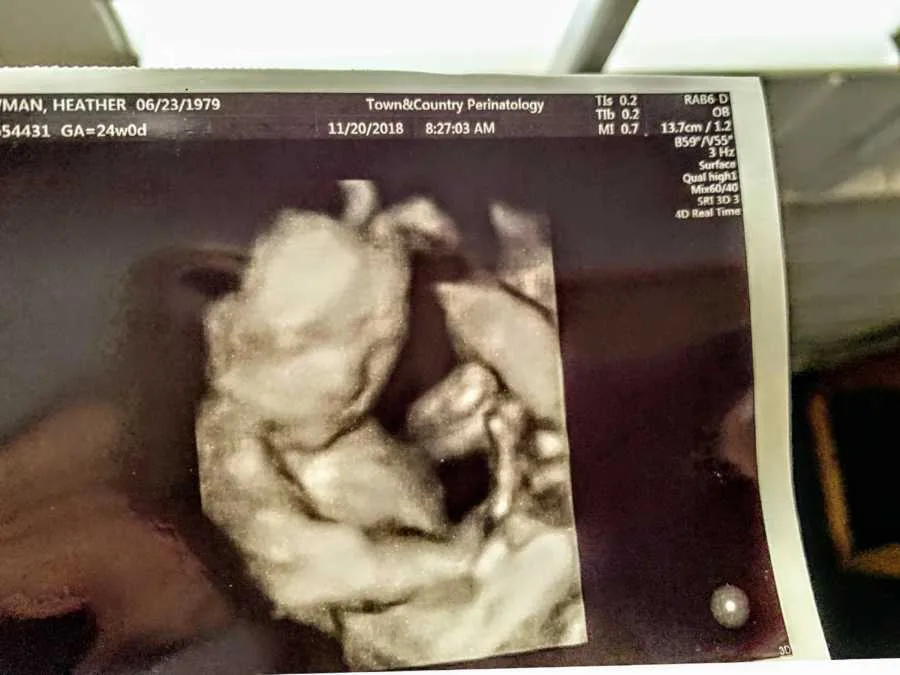

Later, she got a few tests and scans done to figure out if there was any other issue other than the low egg count, and she was right about it, as she was now also diagnosed with a unicornate uterus. It did not mean that she could not get pregnant, but the chances of miscarrying and having a pregnancy with complications were higher. Thus, at the age of 39, she switched to IVF. She transferred two embryos and soon was pregnant, with twins AGAIN! This time again, it was a boy and a girl.

Although the doctor immediately gave her a suggestion to reduce the number of babies for this reason, she refused and found a doctor who would enlighten her about the hope of a safe delivery of the twins. However, at 17 weeks, the scans revealed only one heartbeat.